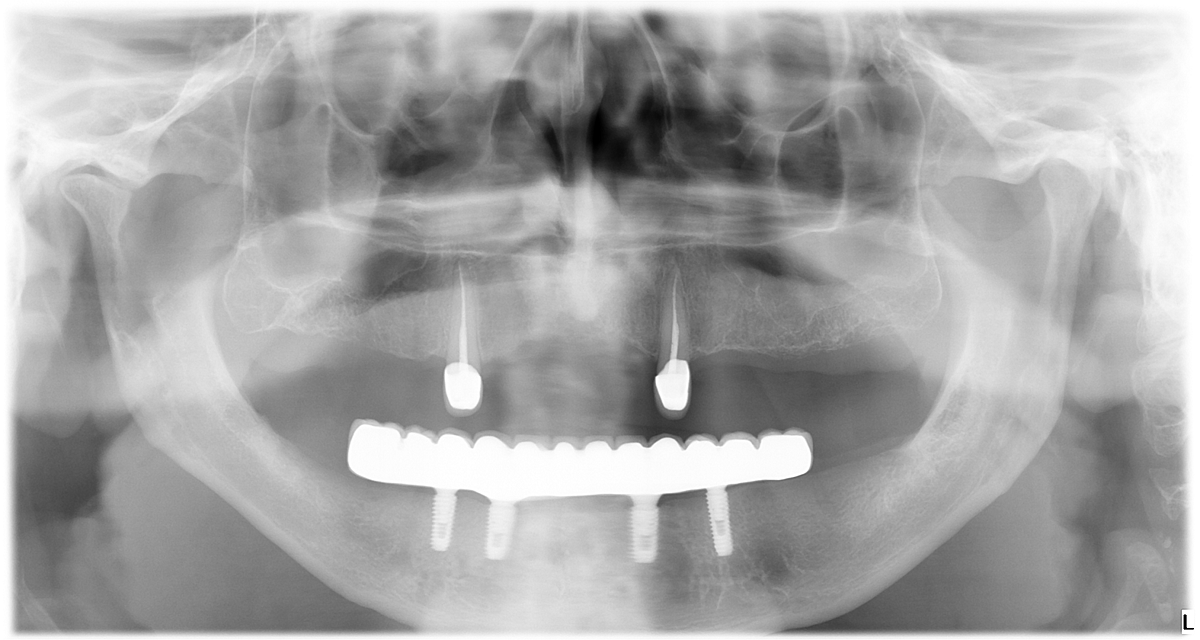

Металлокерамический мостовидный протез на нижней челюсти на балочной конструкции с винтовой фиксацией с опорой на 4-ёх имплантатах ( система Osstem).

Рентген снимок ОПТГ

2. Изготовлены металлокерамические коронки на клыки (13 и 23 зубы).

4. На нижнюю челюсть установлен металлокерамический мостовидный протез на балочной конструкции с винтовой фиксацией с опорой на на 4 мплантата.